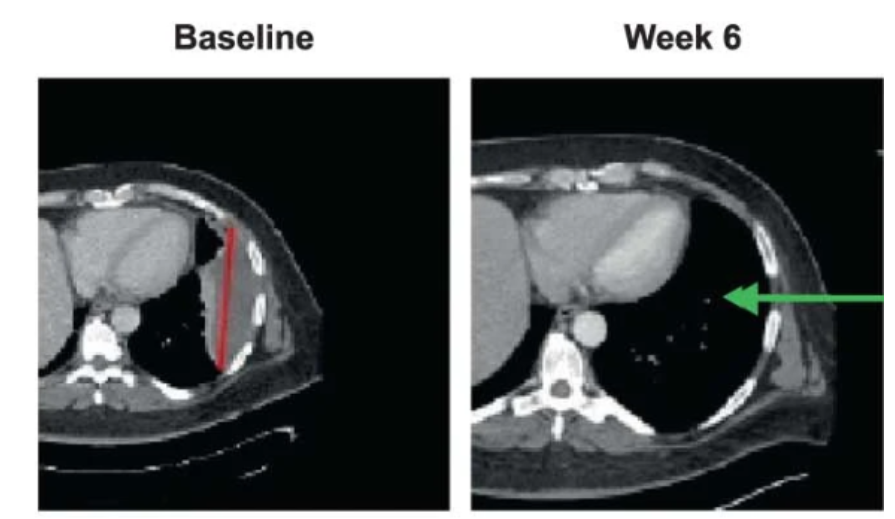

另一位幸运的晚期滑膜肉瘤患者,仅接受6周治疗,胸膜的巨大转移病灶就全部消失,达到了完全缓解(CR)。